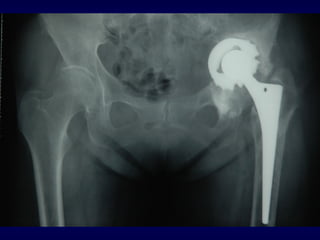

Paprosky 2A

Paprosky 1

Follow up a 3

anni